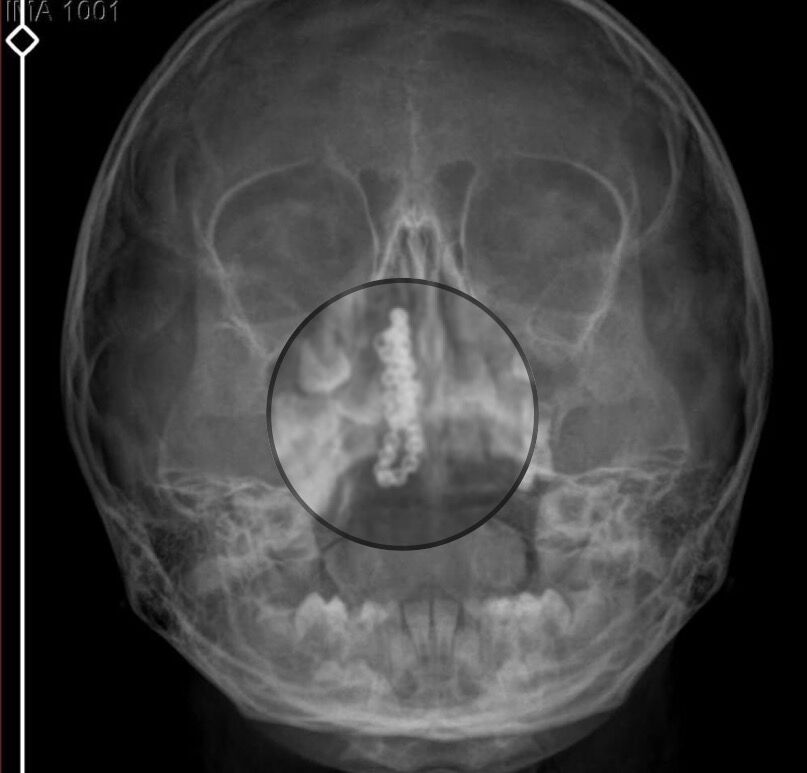

Devlet hastanesindeki doktorun incelemesi ve kapsamlı röntgen çekilmesi sonrası Polen'in burnunda metal cisim olduğu fark edildi. 2 yıldır burunda kaldığı değerlendirilip, küçük top şeklinde tırnak makası zinciri olduğu belirlenen cisim, başarılı ameliyatla çıkarıldı.

Böyle bir ihmalkarlık olabilir mi? Özel hastaneye gidiyoruz, paramızla rezil oluyoruz. Zincir, 2 yıldır burnunda ve devletimizin hastanesinde iyi bir doktorumuz zinciri ortaya çıkarıyor, kızım ölümden dönüyor. Ben sonuna kadar bu işin peşini bırakmayacağım. Sonuna kadar hukuk mücadelesi vereceğim. Bu da diğer hastalarımıza ibret olsun. İşte, bakın koca bir zincir. 'Bulguya rastlanılmadı' deniliyor" dedi.

Ameliyattan çıkan parmağım kadar zincir. Devlet hastanesindeki doktor da 'Bu nasıl gözden kaçılabilir? Böyle bir pozisyon nasıl görülmeyebilir?' yorumunda bulundu. Allah'a şükür olsun atlattık. Şu anda durumu, vaziyeti iyidir. Ben şuna inanıyorum doktor da bir şans işidir. Bakın paramızla özele gideriz ya hani bizde, daha iyi ilgilenirler. Oysa devlet hastanesindeki doktorumuz olayı meydana çıkardı" diye konuştu.